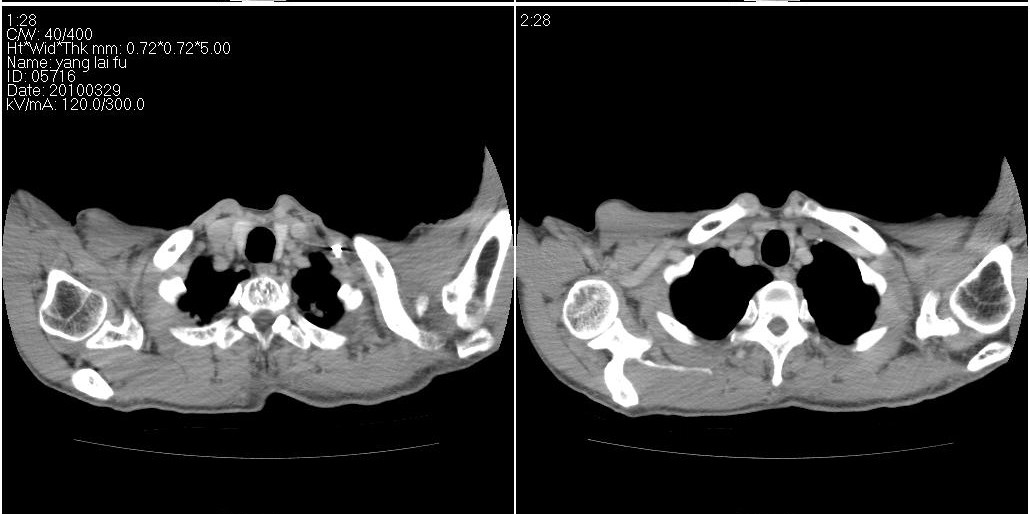

以下是ct检查的情况:

考虑右肺下叶炎症可能性大?未除占位,建议增强。右下肺肺不张

右下胸壁皮下气肿。

右肺中叶阻塞性不张及肺炎,高度怀疑支气管占位,建议纤支镜检查!

右中肺阻塞性炎症,建议纤支镜!双下支扩感染。

1)右肺中叶慢性炎症并支气管扩张,节段性肺不张。2)两肺下叶支气管扩张。